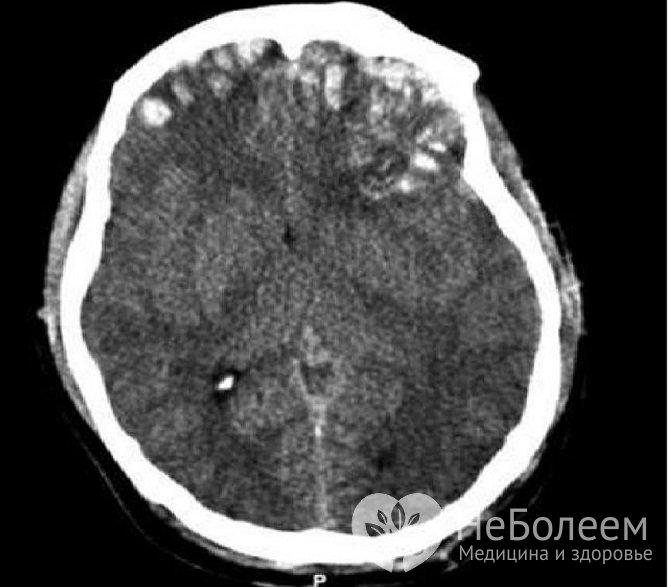

Для уточнения диагноза проводится компьютерная томографияВ диагнозе при очаговых поражениях обязательно определяется:

Тяжесть травмы определяют по общемозговым, стволовым и очаговым симптомам. Чтобы оценить степень поражения головного мозга и определить, как его лечить, проводят компьютерную томографию.